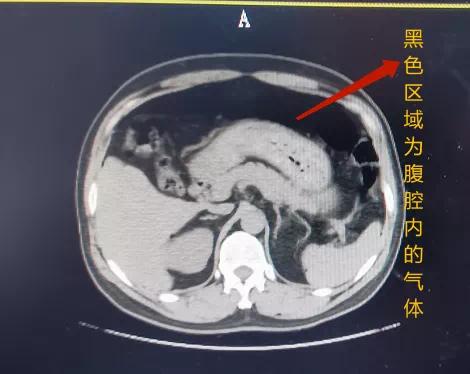

高压气体一旦进入人体

首先遭殃的就是 直肠、结肠、盲肠